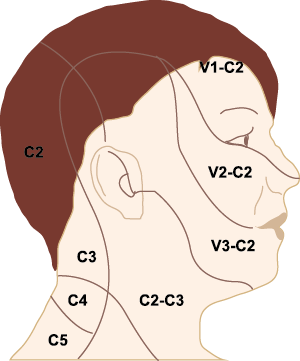

El dolor de cabeza asociado con un ataque de migraña, puede incluir la región frontal, temporal, parietal, occipital y cervical alta, es consecuencia de la activación del sistema trigeminovascular. (Figura 10)

La inervación nociceptiva de la vasculatura intracraneal y las meninges incluye proyecciones axonales no mielinizadas (fibras C) y mielinizadas delgadas (fibras Aδ), principalmente a través de la división oftálmica (V1) del nervio trigémino, pero también, en menor medida, a través del nervio maxilar. (V2) y divisiones mandibulares (V3). También hay inervación neuronal de la duramadre desde los ganglios de la raíz dorsal cervical (24) (Figura 12).

Hay una proyección aferente central desde el ganglio del trigémino que ingresa a la médula caudal del tronco encefálico, a través del tracto del trigémino, que termina en el núcleo espinal del trigémino caudalis (TNC), así como la médula espinal cervical superior (C1–C2). (Figura 16)

Las fibras nociceptivas Aδ y C terminan predominantemente en las láminas superficiales, I y IIo, así como en las láminas más profundas V–VI del TNC y extensión cervical. La estimulación de la vasculatura dural en modelos animales, incluidos los senos transverso y sagital superior y la arteria meníngea media, da como resultado la activación de las neuronas en las regiones TNC, C1 y C2 de la médula espinal cervical, conocidas en conjunto como el complejo trigeminocervical (TCC).

Estos datos sugieren que el núcleo del trigémino se extiende hasta el asta dorsal de la región cervical superior en un continuo funcional que incluye la extensión cervical, ello explica la distribución de la percepción del dolor en la migraña sobre las regiones frontal y temporal, además de la participación de parietal, occipital y regiones cervicales superiores(27).